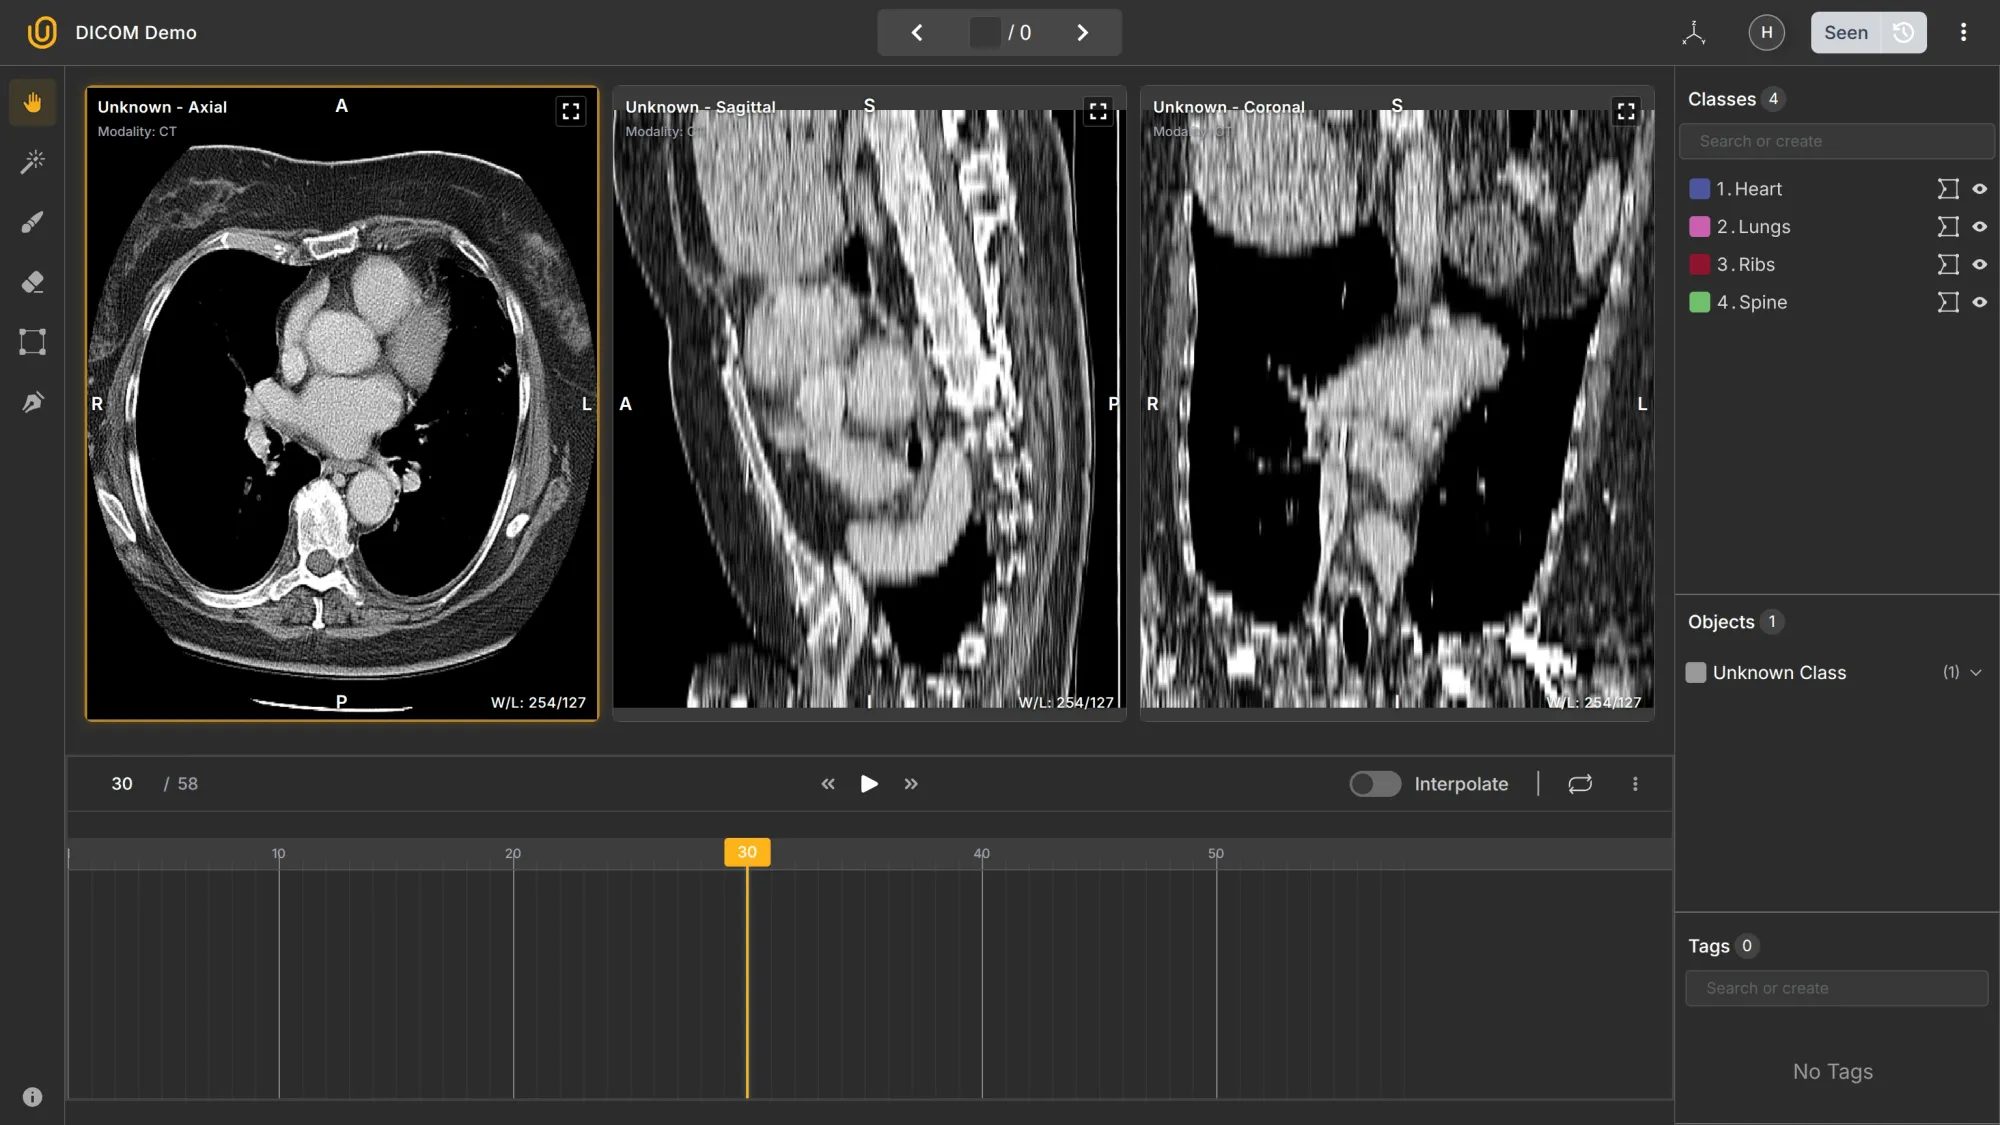

- Multi-slices → A DICOM study can contain dozens or hundreds of consecutive 2D slices of the same body region (e.g., 58 slices through the chest).

- 2D and 3D → Each slice is 2D, but when combined, they form a 3D volume. Annotation tools can reconstruct or navigate through that volume interactively.

- Multi-planes → You can view the same dataset in different planes:

- Axial (top-down)

- Sagittal (side)

- Coronal (front)

Together, these make DICOM data volumetric and spatially consistent — that’s why it’s used for medical imaging rather than formats like PNG or JPEG.

For starters, what is Axial, Sagittal, and Coronal? What is interpolation in this context? 3D and 2D? Multilayers? 58 frames in the Axial section? Understanding the conventions, let alone annotating medical images, is not an easy task.